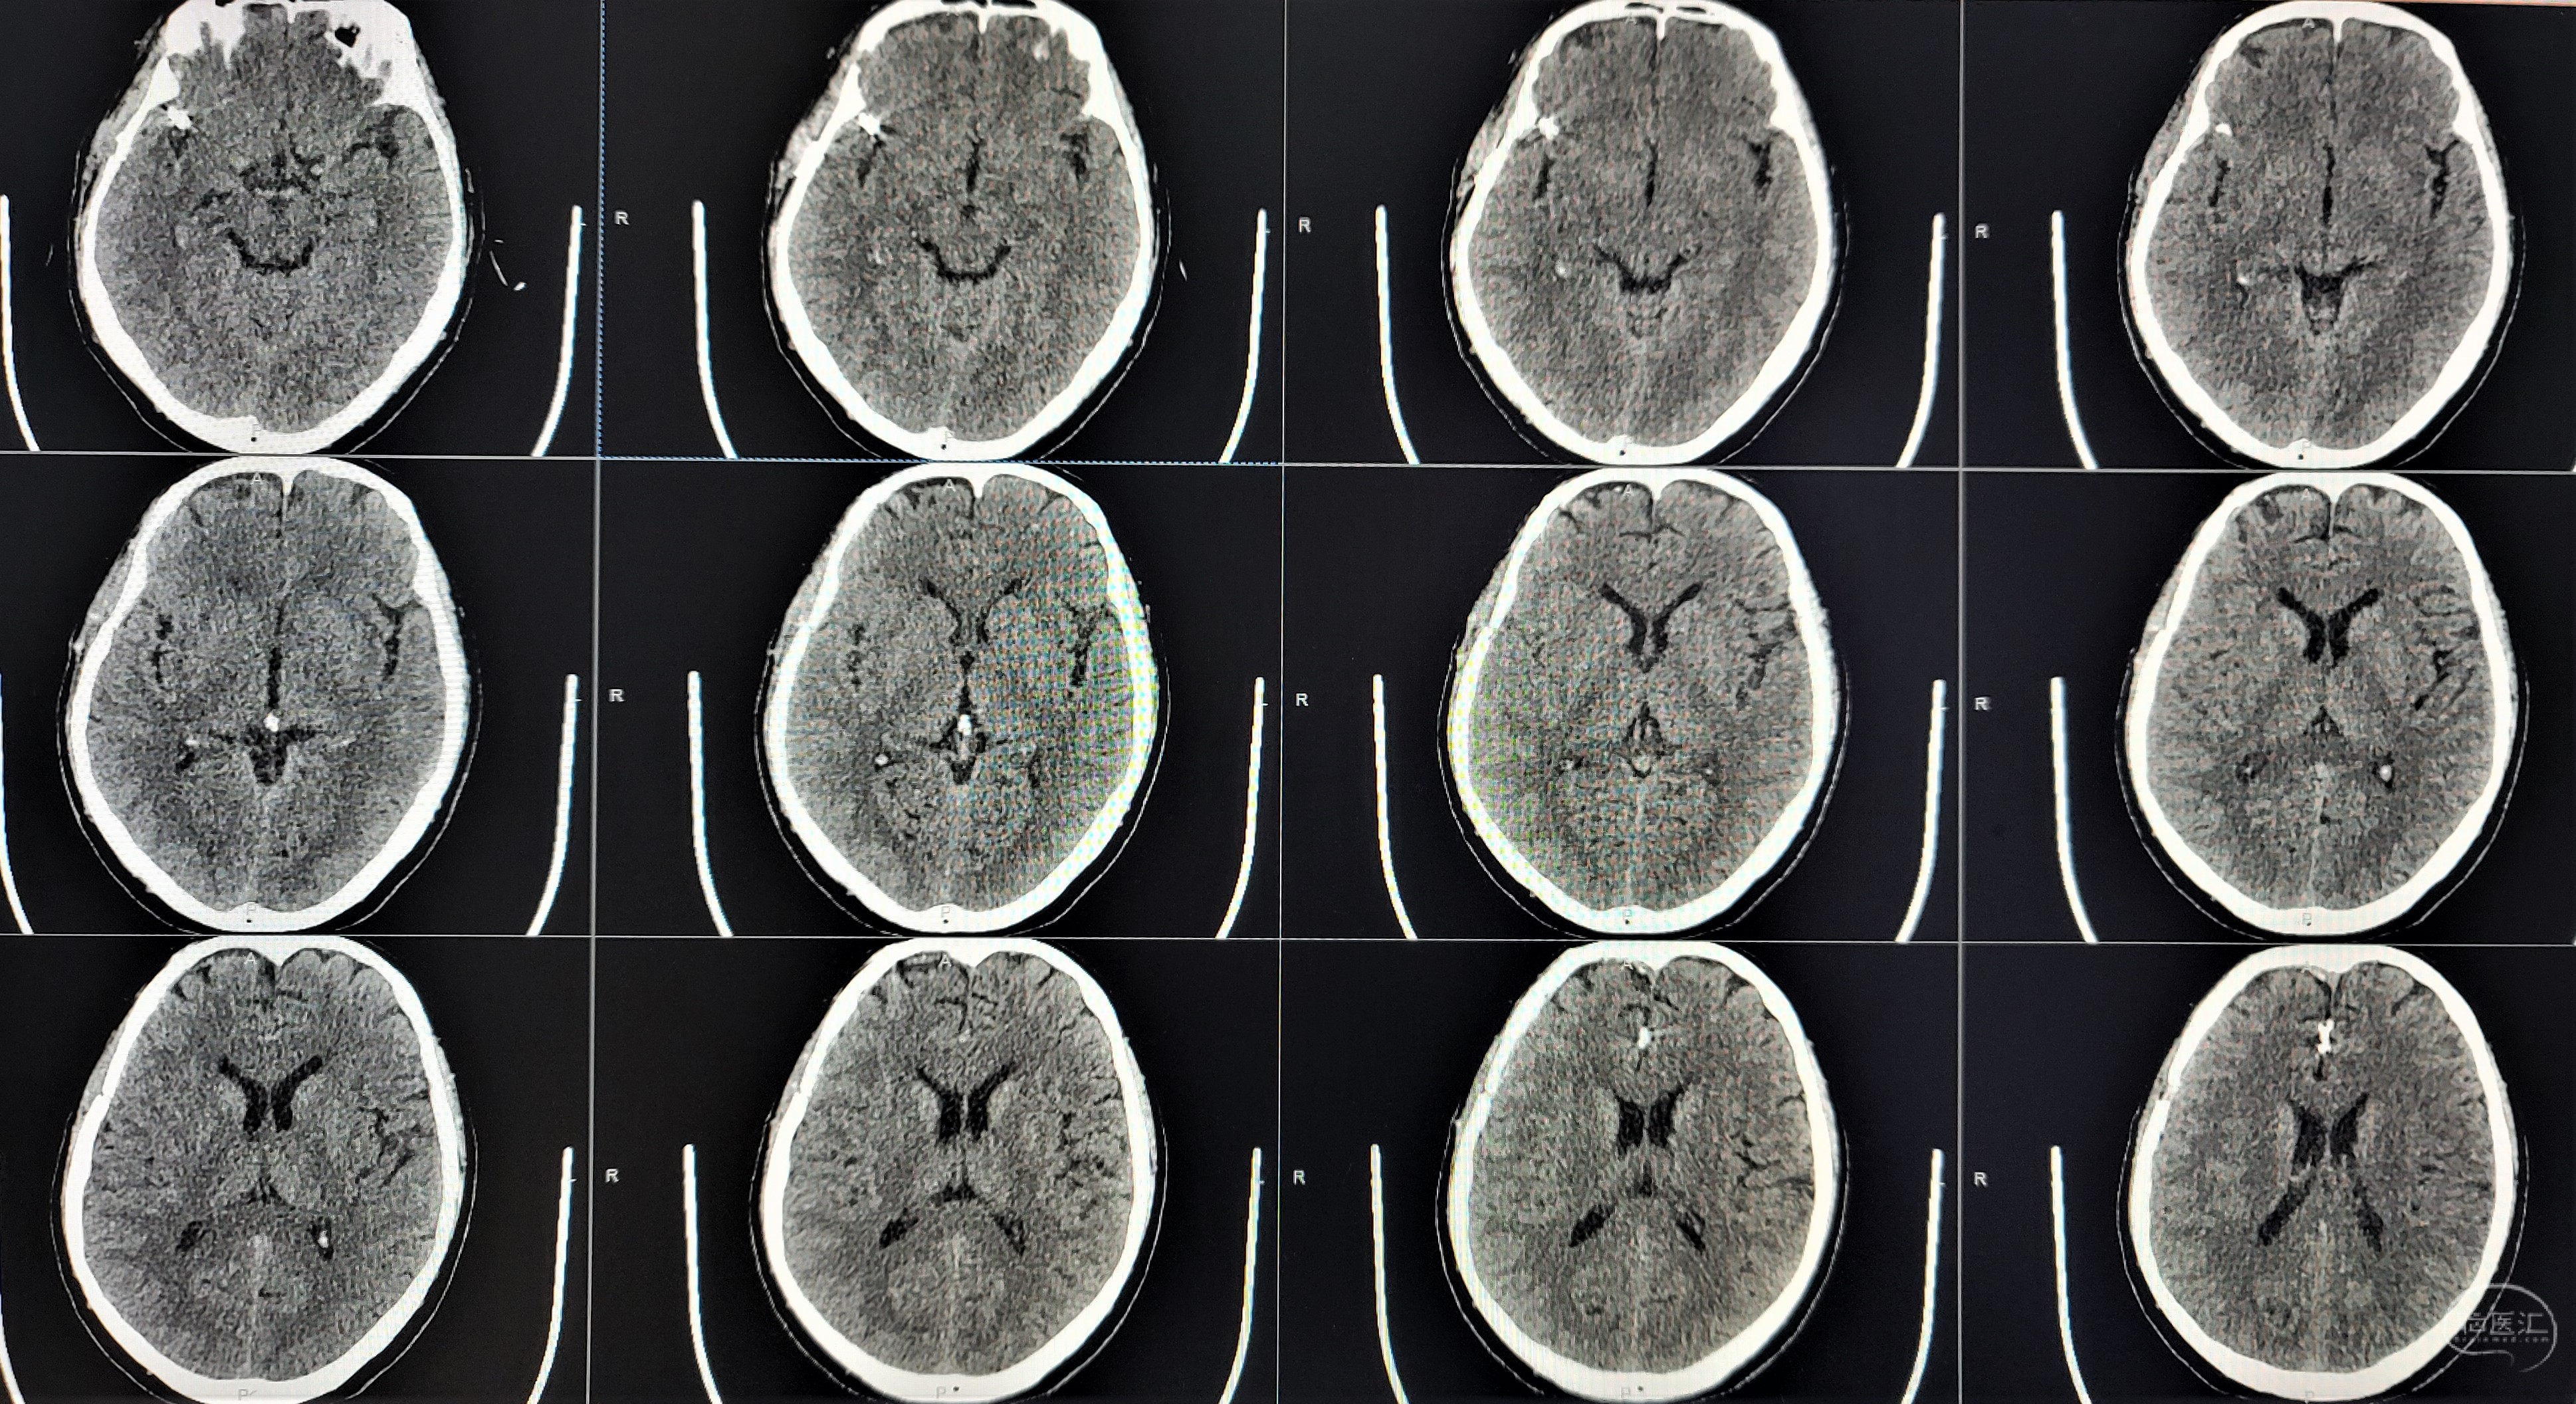

术后1月复查头颅CT及CTA

CTA显示大脑中动脉瘤消失,分支血管保留完好。

CTA显示A2/A3动脉瘤消失,近端分支血管保留完好。